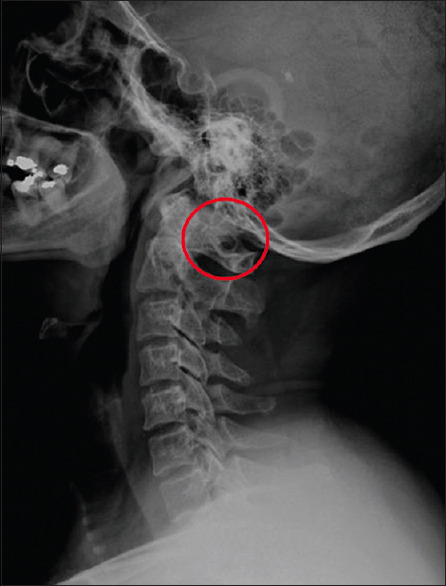

Background and objectives: Ponticulus posticus (PP), also known as arcuate foramen or Kimmerle's anomaly, is an atlas (C1) bone anomaly in the form of a bone bridge. This study aims to determine the prevalence of PP in two hospitals in Surabaya, Indonesia, and to determine the risk factors for PP and its impact on the thickness of the C1 lamina.

Results: The study found a prevalence of PP of 15.7%. The mean thickness of the posterior arch lamina with PP was 3.3 ± 0.95 mm on the right side and 3.4 ± 1.0 mm on the left side. Although these figures are not statistically significant, both were thinner than the lamina without PP. The study also found that the prevalence of PP increases with age, with a significant value of P < 0.001.